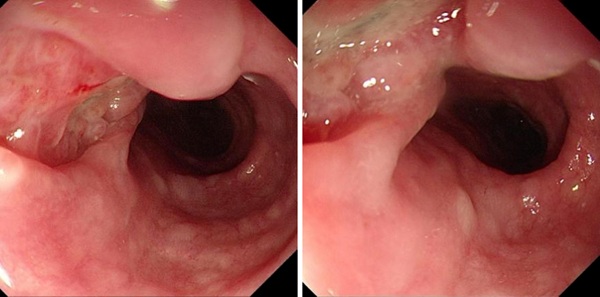

胃镜进入食管后,眼前的画面却和预想中的食管癌并不一样。

我看到的不是典型的肿块型或浸润型癌变,而是一个凹陷性溃疡样病灶。

这个病灶有几个非常特别的地方:

· 边缘比较锐利

· 内部呈结节样改变

· 局部可见紫蓝色薄膜样改变

病变位于距门齿约 27~30 cm 处

胃镜表现